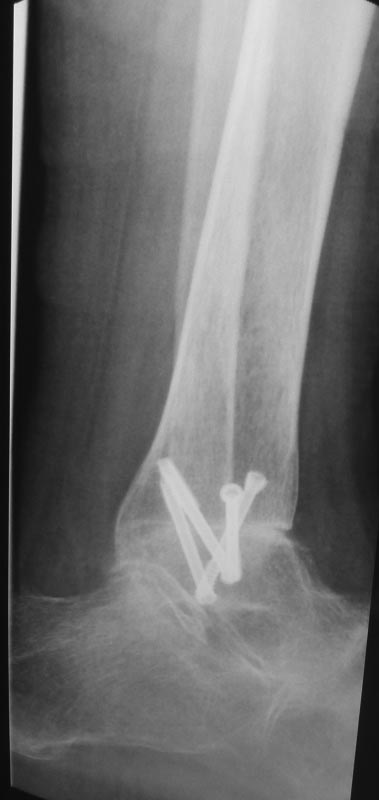

Вот обещанный в чем-то похожий случай. Пациентка 58 лет с тяжелым ревматоидным артритом. Оперировал в 2013 г. В одну сессию сделал чрескожно повторную операцию на стопе (раньше где-то оперировали, пациентка приехала издалека) и малоинвазивный артродез голеностопного сустава (имелась варусная деформация, как компенсация вальгуса колена, на фоне выраженной ревматоидной артропатии). А через неделю – протезирование коленного сустава (фиброзный анкилоз после когда-то выполненной синовэктомии, грубая вальгусная деформация). Понятно, что неделю между операциями стопа торчала в сторону и не была опороспособной. Основное пожелание по коленке было, чтобы сгибалась хоть немного для походов в театр. В конечном счете, сустав сгибался до 90 гр. Фотография стоя была прислана через 2 года после операций. А через 3 года, прошедшим летом, пациентка упала с лестницы: перипротезный перелом бедра. Через 5 дней приехала оперироваться. Отсюда отек на фото стопы. Что интересно, через 2 мес. после остеосинтеза пациентка написала, что только теперь, после перелома, смогла ощутить опору всей поверхностью стопы. До этого пользовалась индивидуальными стельками.